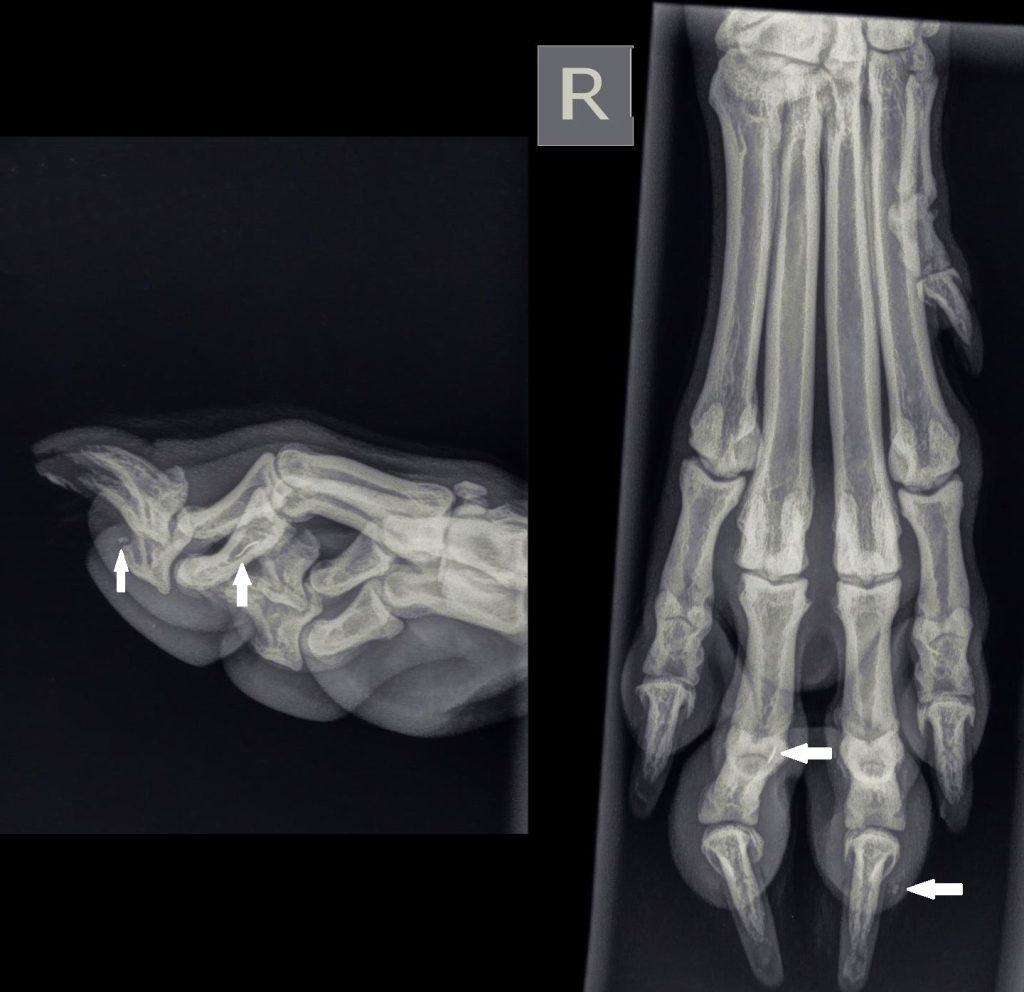

Röntgenfoto’s

Op de röntgenfoto van het pootje van Xander was een klein wit streepje zichtbaar onder het 4e teentje (we tellen altijd vanaf de duim, dat is nummer 1). Gezien de mate van witheid, leek het een stukje metaal te zijn. Tevens zat er nog een klein stukje steen net onder de nagel van de 3e teen.

Het stukje metaal kan zeker kreupelheid veroorzaken. In overleg met zijn eigenaar hebben we besloten een nieuwe afspraak te maken voor Xander, aangezien het stukje te diep leek te zitten om het met een lichte sedatie in de spreekkamer te verwijderen. Dus zouden we operatief gaan proberen om het stukje metaal te verwijderen.